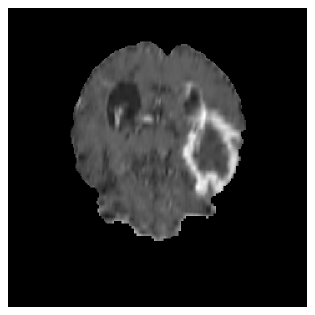

Appendix A Qualitative results

Figures 4 and 5 present the segmentation results for a patient from the BRATS dataset, visualized on a randomly selected slice. Figure 4 illustrates how tumor segmentation evolves over multiple episodes in S1 across different approaches including cumulative, naive, our approach, and the best buffer-free strategy (SI, =2). The cumulative approach, which trains on all encountered datasets together, maintains segmentation consistency across episodes but introduces significant amounts of false positives, particularly in the upper left area of the brain images. These misclassifications highlight its inability to generalize well across datasets despite access to all previous data. The naive approach, which learns sequentially without any continual learning strategy, suffers from severe catastrophic forgetting. While it initially segments well, performance deteriorates over episodes, leading to a near-complete loss of segmentation capability by the final episode. The SI (=2) approach, a regularization-based buffer-free CL strategy, performs reasonably well in early episodes but shows a significant performance decline over time. By the last episode, much of the tumor was no longer segmented, indicating difficulty in retaining prior knowledge. In contrast, our proposed approach initially produces more false positives but progressively refines its segmentation. By the final episode, it accurately retains the tumor region while minimizing misclassifications, demonstrating strong knowledge retention and adaptability across episodes. This suggests that our approach effectively mitigates catastrophic forgetting while maintaining segmentation performance over sequential learning.